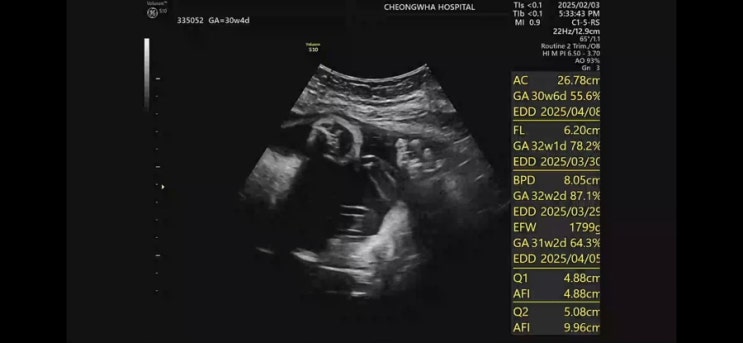

[30주] 안솔이 오랜만 ?

3주만에 본 안솔이 1kg에서 1.7kg이 되어 있었다. 두배 정도는 더 커야 나오는건데.. 지금도 배 찢어지겠어...